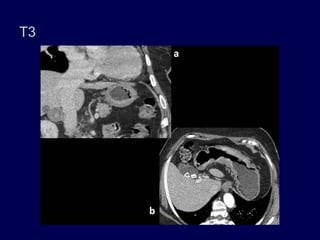

Estadio III: (a) El tumor invade la muscularis propia y la serosa. Adenopatías

en la cadena ganglionar. (b) Tumor en el antro con gruesa infiltración de la

grasa perigástrica.

T3